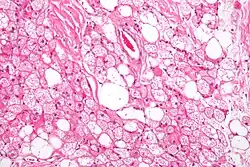

Los tumores se parecen histológicamente a la grasa parda. Se reconocen cuatro tipos histológicos, pero uno es el más frecuente (típico). Se observa un entorno rico en vascularización .

- Tipo lobulillar: grados variables de diferenciación de células uniformes, redondas a ovaladas con células eosinófilicas granulares con bordes prominentes, que se alternan groseramente con adipocitos multivacuolados. Por lo general, hay pequeños núcleos ubicados en el centro sin pleomorfismo. Las células tienen grandes gotas de lípidos citoplasmáticos grandes diseminados por todas partes.[1][2]

Hibernoma (aumento intermedio).